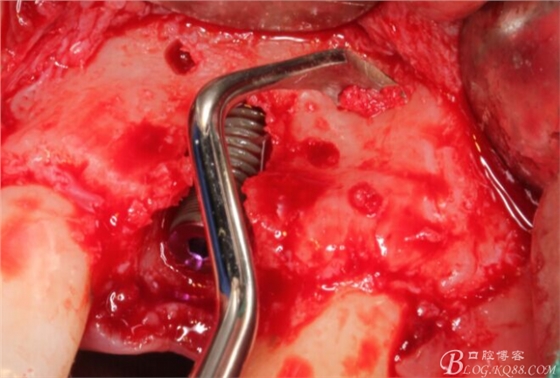

徹底搔刮拔牙窩,偏腭側(cè)備洞

順利植入植體,扭力30N。三壁骨,感覺美美的。

刮自體骨覆蓋種植體表面。

血液調(diào)扮BIO-OSS骨粉覆蓋術(shù)區(qū)。

蓋生物膜,固定。